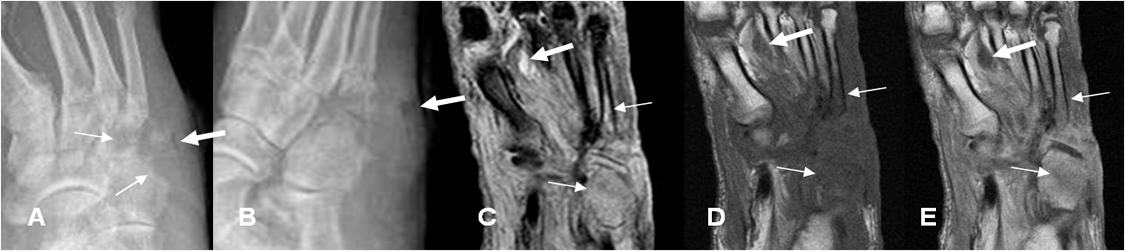

Fig 64 D. Artritis séptica.

A: Rx AP y B: Rx oblicua. Ausencia del 5º metatarsiano, por amputación previa. Lesiones líticas en la cuña lateral, el cuboides y la base del 4º metatarsiano, por osteomielitis. Existe aire en los tejidos blandos, por la formación de absceso. (Flechas gruesas).

C: RM coronal en STI, D: RM coronal en T1 simple y E: RM coronal en T1 con contraste.

Huesos del medio pie hipointensos en T1, hiperintensos en STIR y con realce del contraste. (Flechas delgadas). Adicionalmente hay pequeña colección de tejidos blandos, entre el 1º y 2º metatarsianos, sin realce. (Flecha gruesa).